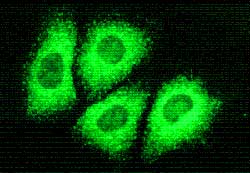

Cuando alguien se infecta con el virus de la hepatitis C, su cuerpo comienza a producir anticuerpos para destruirlo. Sin embargo, la mayoría de las veces, los anticuerpos no logran identificar adecuadamente al virus y la infección permanece a largo plazo. De hecho, gran parte de las personas infectadas con este virus no saben que lo están debido a que no experimentan síntomas o a que pasan cerca de 13 años de media hasta que los síntomas se manifiestan. Se desarrolla en dos fases: